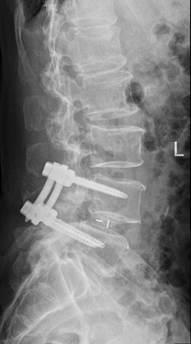

术后影像显示,螺钉位置良好